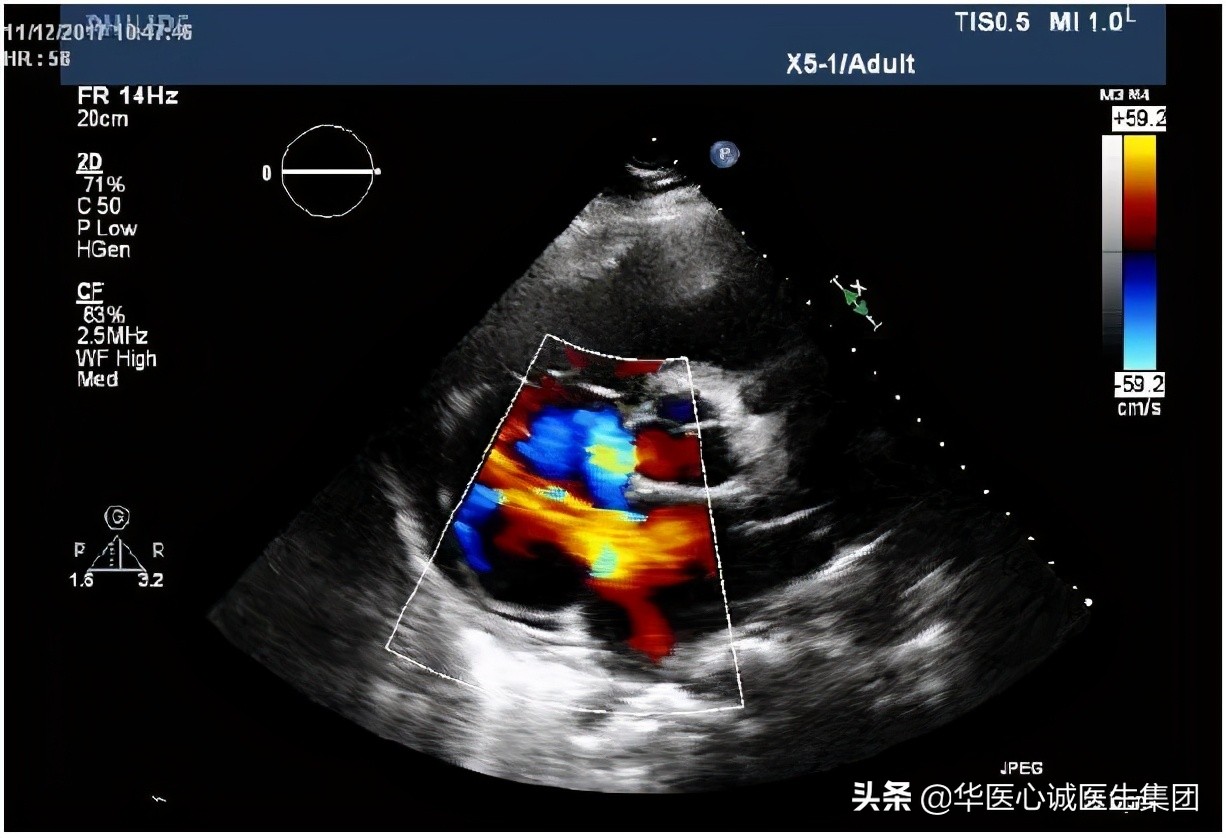

三尖瓣返流压差48mmHg,右房压至少15mmHg ➜ 肺动脉收缩压也高 ➜ 到底是因为房缺分流量太大造成的,肺循环血流量增多造成的,还是左室压高、左房压高造成的? 其实是相互叠加的 。为什么会有这样的判断?

左图:入院时测量的房缺分流速度和压差(19mmHg),右房压至少15mmHg ➜ 导致左房压很高,预计40mmHg ➜ 充分提示左室充盈压非常高。

右图:治疗1周后,血压下降,左房与右房的压差降至4mmHg,接近正常水平。因为左房压下降,左心衰得到控制,患者症状立即好转。